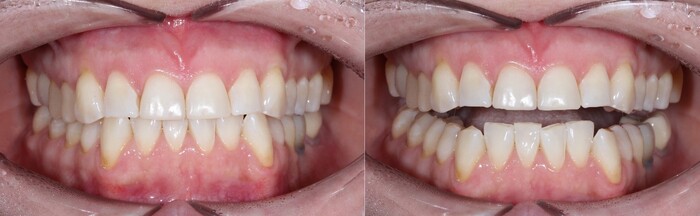

Если вы еще помните, то статья про необходимость исправления прикуса до установки имплантатов. Было бы странно, если бы описывая данный клинический случай я бы не упомянул, что у девушки изначально были выраженные проблемы с прикусом, патологическая стираемость зубов и сколы.

И вот эти проблемы дали о себе знать. Июнь 2023 года, спустя каких-то 5 лет после установки коронки на 7й нижний имплантат винт ломается и в нем.

Прикус:

За эти годы ситуация усугубилась, стираемость зубов прогрессировала.

Вот как выглядели зубы в 2018 году:

А это через каких-то 3 года, 2021:

Обратите внимание, как сильно стерлась верхняя «двойка» и нижний клык:

Ниже ситуация от июня 2023:

Есть такое понятие, как клыковое ведение (или клыковая дезокклюзия) – это разобщение задних зубов во время боковых движений нижней челюсти. Иными словами, (прочтите медленно) при смещении нижней челюсти в сторону, двигаясь клыком нижней челюсти по клыку верхней челюсти на момент контакта бугров, у боковых зубов не должно быть контакта. В данном случае он есть именно на 7ках:

Оранжевым цветом отмечена стираемость зубов, а красным место контакта.

Зубы стерлись, высота прикуса занизилась. В связи с чем появился преждевременный контакт керамической коронки на нижнем 7м зубе (керамика не стирается) и верхним 7м зубом.

(Вы можете отметить, что на 6ке тоже керамическая коронка. Не стоит забывать, что ее переделывали. Следовательно, она была подогнана под истертые зубы).

Поэтому, из-за постоянной перегрузки винт и сломался. Могучий Иван снова достал винт, заменил его на новый и прикрутил обратно ту же самую коронку. Подточил 7й зуб, вывив его из преждевременного контакта с нижним. (снимки сделаны при помощи зеркала) на 3,4,5,6 зубах отпечатана копирка, на 7м нет:

Стоил ли говорить, что не пришлось снова объяснять пациентке о необходимости ортодонтии?